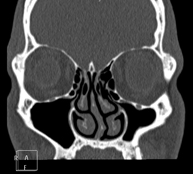

- TC Senos paranasales Prueba radiológica que consiste en obtener imágenes de los senos paranasales de alta definición anatómica, mediante el empleo de un equipo de TC (Tomografía Computarizada). Indicaciones: cefalea, tos crónica, mucosidad, infecciones faciales. Prueba radiológica que consiste en obtener imágenes de los senos paranasales de alta definición anatómica, mediante el empleo de un equipo de TC (Tomografía Computarizada). Indicaciones: cefalea, tos crónica, mucosidad, infecciones faciales.